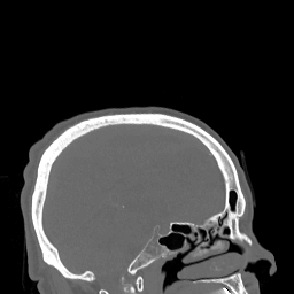

Model-based treatment planning for transcranial ultrasound therapy typically involves mapping the acoustic properties of the skull from an x-ray computed tomography (CT) image of the head. Here, three methods for generating pseudo-CT images from magnetic resonance (MR) images were compared as an alternative to CT. A convolutional neural network (U-Net) was trained on paired MR-CT images to generate pseudo-CT images from either T1-weighted or zero-echo time (ZTE) MR images (denoted tCT and zCT, respectively). A direct mapping from ZTE to pseudo-CT was also implemented (denoted cCT). When comparing the pseudo-CT and ground truth CT images for the test set, the mean absolute error was 133, 83, and 145 Hounsfield units (HU) across the whole head, and 398, 222, and 336 HU within the skull for the tCT, zCT, and cCT images, respectively. Ultrasound simulations were also performed using the generated pseudo-CT images and compared to simulations based on CT. An annular array transducer was used targeting the visual or motor cortex. The mean differences in the simulated focal pressure, focal position, and focal volume were 9.9%, 1.5 mm, and 15.1% for simulations based on the tCT images, 5.7%, 0.6 mm, and 5.7% for the zCT, and 6.7%, 0.9 mm, and 12.1% for the cCT. The improved results for images mapped from ZTE highlight the advantage of using imaging sequences which improve contrast of the skull bone. Overall, these results demonstrate that acoustic simulations based on MR images can give comparable accuracy to those based on CT.